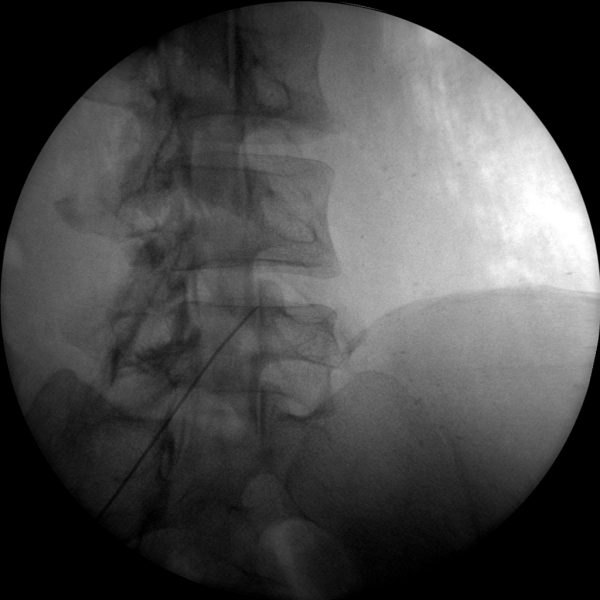

Epidural Injections

The high-resolution 1kx1k images from Skan-C helps pain management professionals visualize the position of the needle in relation to the epidural space, ensuring accurate and effective treatment.